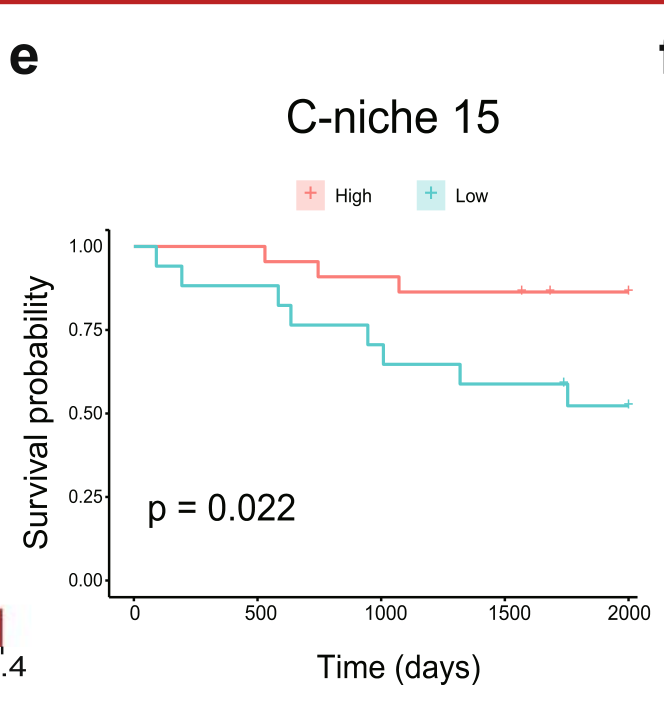

Wang et al., 2025

SOAPy: a Python package to dissect spatial architecture, dynamics, and communication

Can patients be grouped into distinct subtypes based on the composition of their spatial tissue niches?

Condition Dimension

N/A

Data Components

Biological Annotation

Data

Modality

Imaging-based

Resolution of observation

Field of view

Visualized Elements

RelationshipStatistic

Biological

Systemic/Integrative

Abstraction

Complete

Chart Type

Heatmap

Communicative/Contextualization

Highlighting

Comparative Design

Explicit encoding

Layout

Linear

Scalability Strategy

Summay/Aggregate